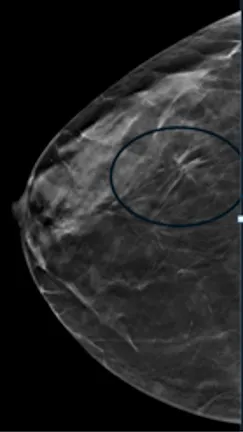

Compare these two images. You can see the benefits of 3D tomosynthesis. A small cancer (circled) on tomosynthesis slices in image A (left) is not apparent in the standard 2D mammogram, image B (right) of the same patient and same projection.